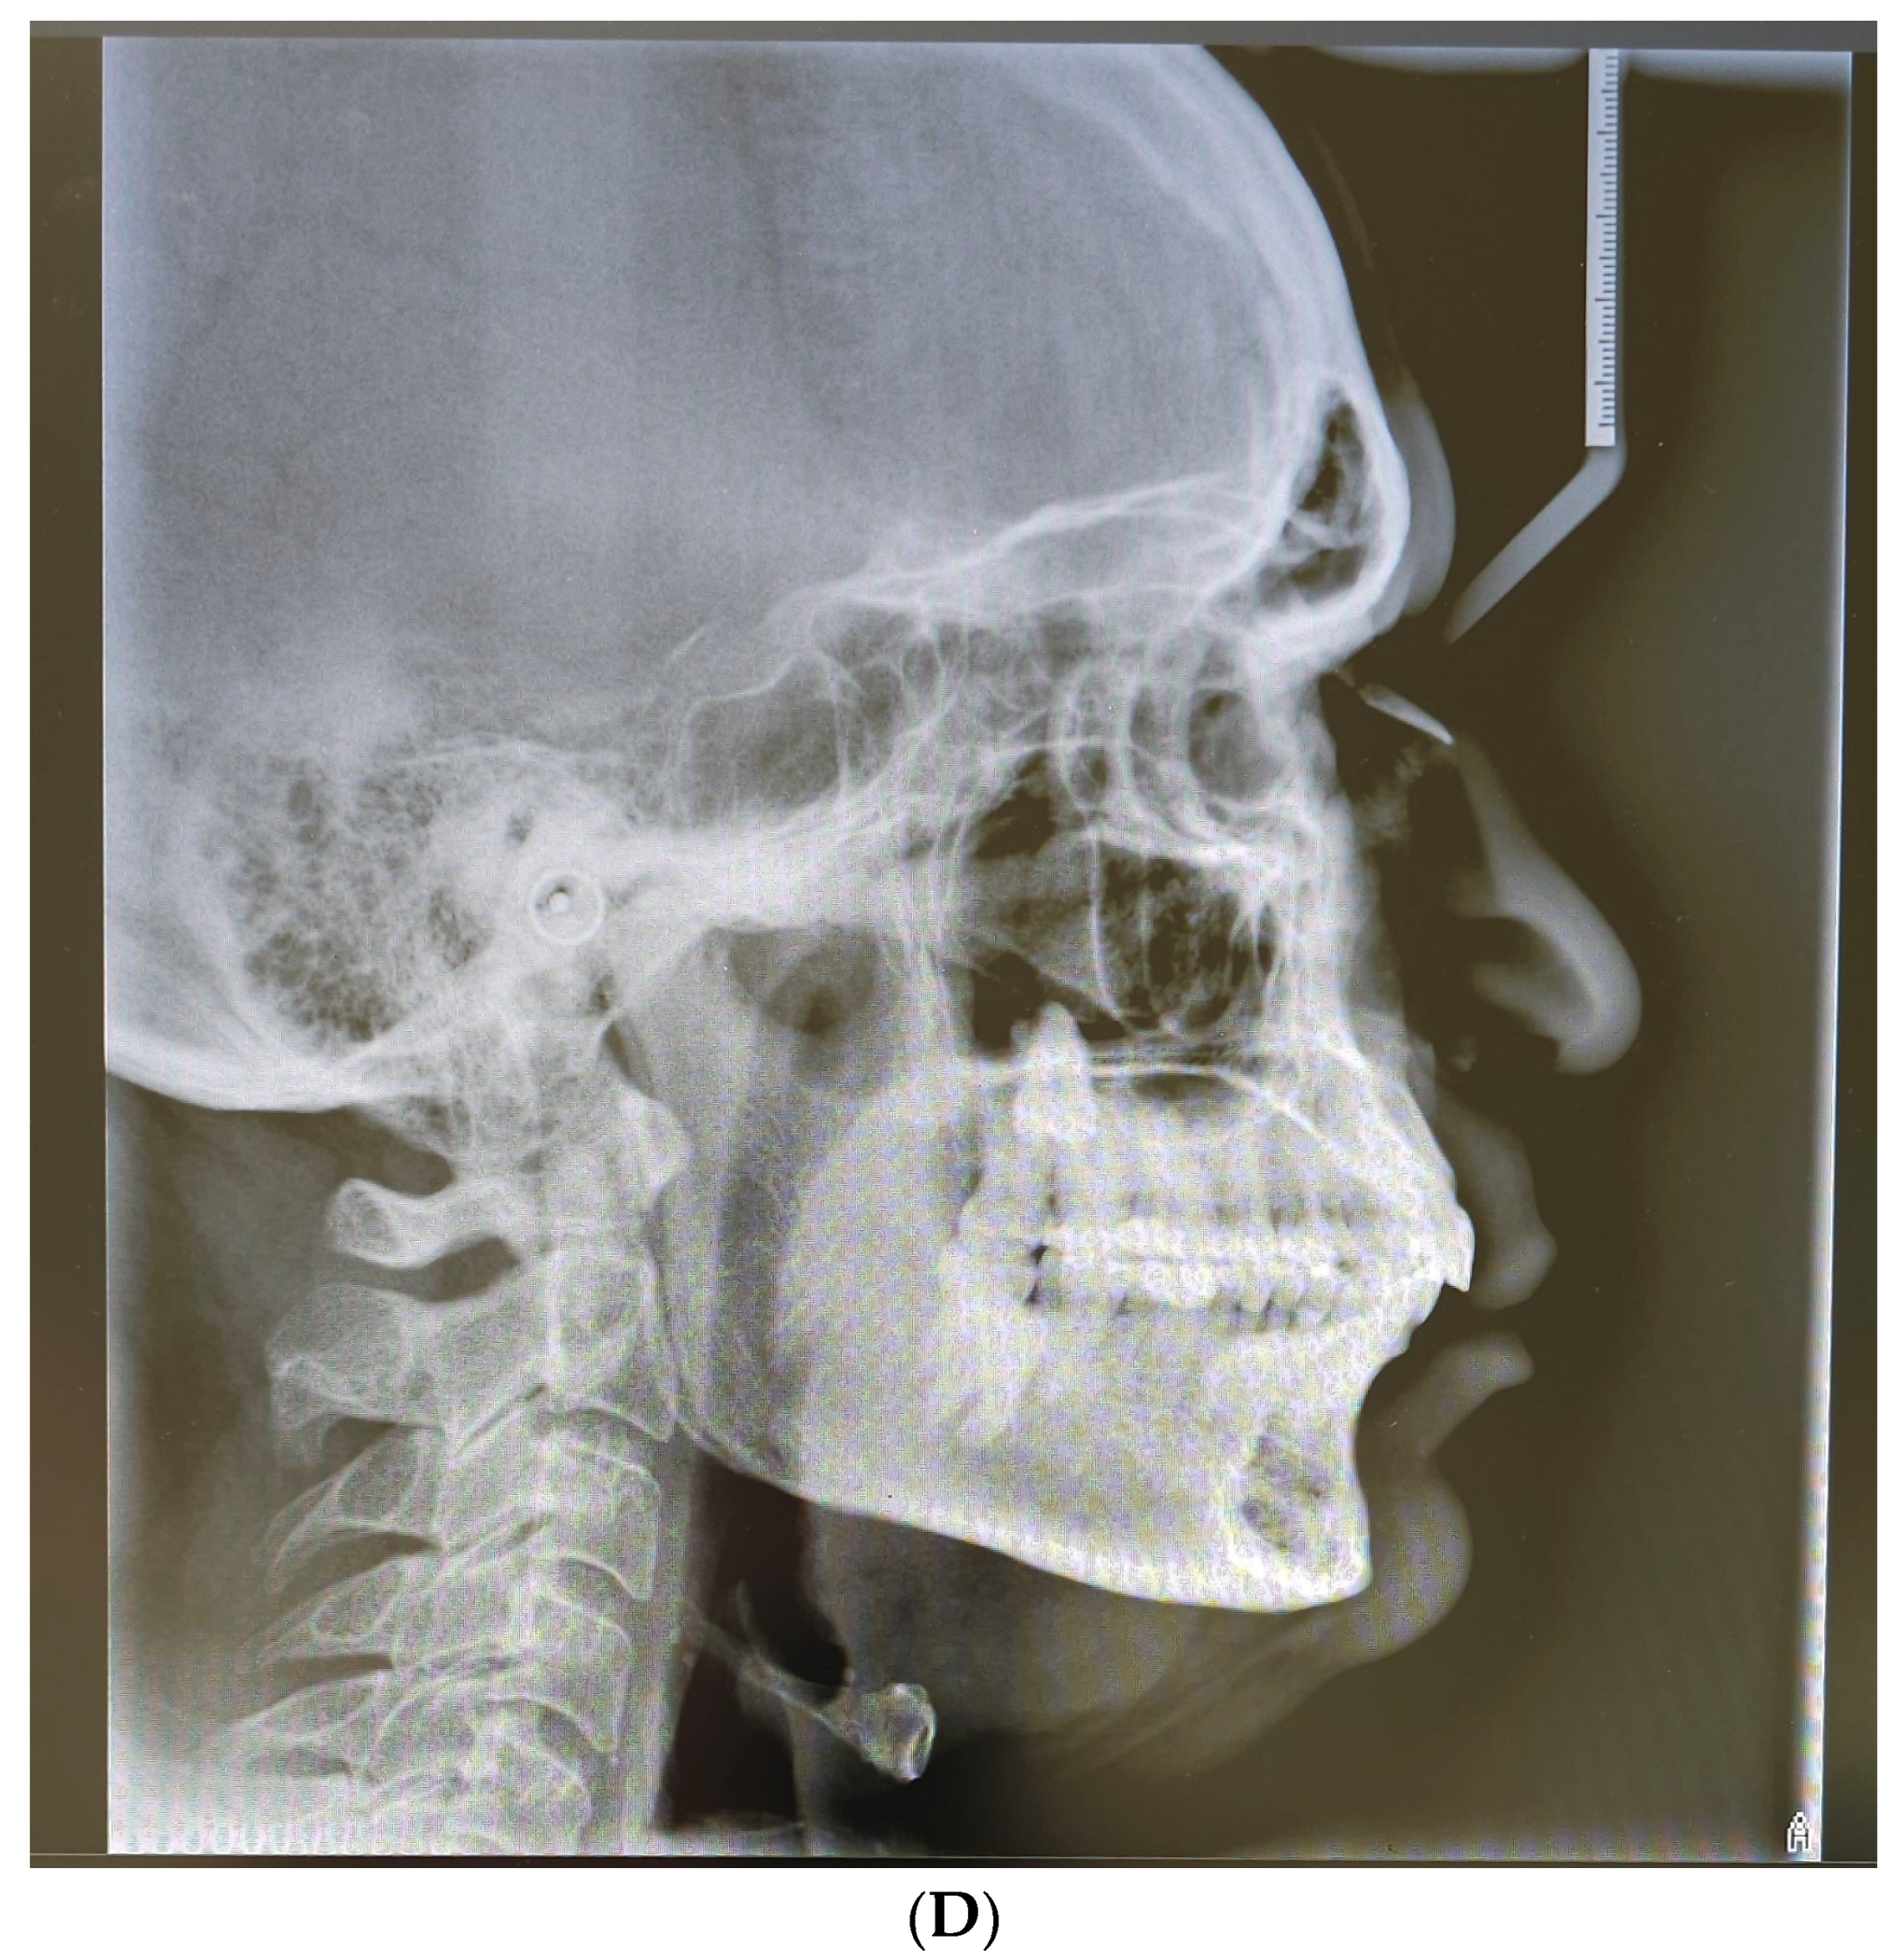

2. Case Presentation